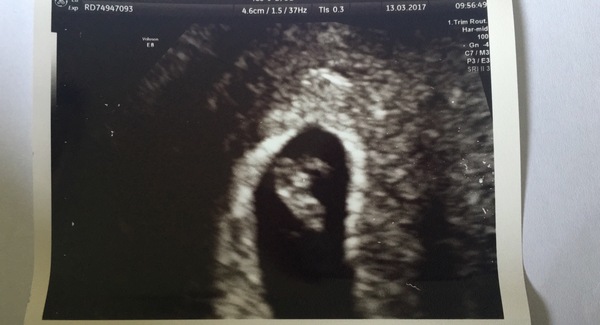

Just wanted to let everyone know my scan went ok... measured somewhere between 4 days to a week behind i should have been 7+4 going off LMP but there was a good strong heartbeat and the doctor was pleased which reassured me.

Now just a long old wait until 12 week scan although i am not even sure when that is yet!